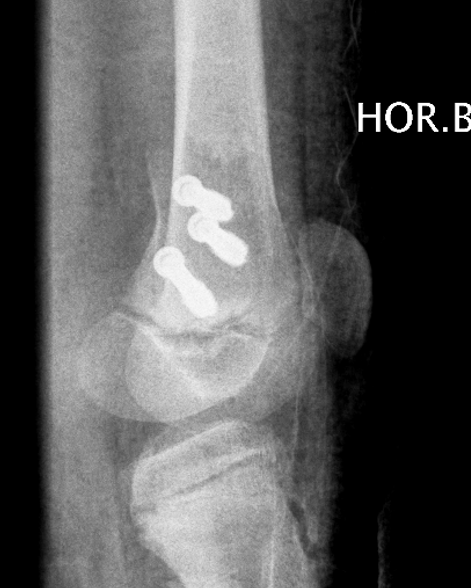

Partial growth arrest / angular deformity

SH2Dis femurDis femur

Management

CT / MRI - assess percentage of bony bridge

Bony bridge < 50%

- excision and fat graft

- manage angular deformity with 8 plates / osteotomy

Bony bridge > 50%

- hemi-epiphysiodesis

- may need later correction of LLD and angular deformity